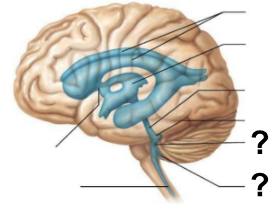

What are the two apertures, labeled “?”, through which CSF exits the fourth ventricle to enter the subarachnoid space?

The median aperture and the lateral apertures